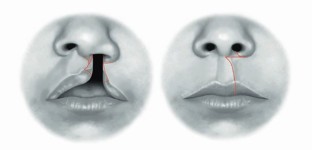

Fisher D M. Unilateral cleft lip repair: an anatomical subunit approximation technique. Plast Reconstr Surg 2005; 116: 61-71.

El Magheraby M F, Ghozlan N A, Ashry M H, Abouarab M H, Farouk A. Comparative study between fisher anatomical subunit approximation technique and Millard rotation - advancement technique in unilateral cleft lip repair. Alexandria J Med 2021; 57: 92-102.

Kwong J W, Cai L Z, Azad A D et al. Assessing the Fisher, Mohler, and Millard techniques of cleft lip repair surgery with eye-tracking technology. Ann Plast Surg 2019; DOI: 10.1097/SAP.0000000000001911.

Patel T A, Patel K G. Comparison of the Fisher Anatomical Subunit and modified Millard Rotation-Advancement Cleft Lip Repairs. Plast Reconstr Surg 2019; DOI: 10.1097/PRS.0000000000005847.

Suchyta M, Azad A, Patel A A, Khosla R K, Lorenz H P, Nazerali R S. Applied Online Crowdsourcing in Plastic and Reconstructive Surgery: A Comparison of Aesthetic Outcomes in Unilateral Cleft Lip Repair Techniques. Ann Plast Surg 2020; DOI: 10.1097/SAP.0000000000002389.

Millard D R Jr. A radical rotation in single harelip. Am J Surg 1958; 95: 318-322.

Millard D R Jr. Rotation-advancement principle in cleft lip closure. Cleft Palate J 1964; 12: 246-252.

Mohler L R. Unilateral cleft lip repair. Plast Reconstr Surg 1987; 80: 511-517.